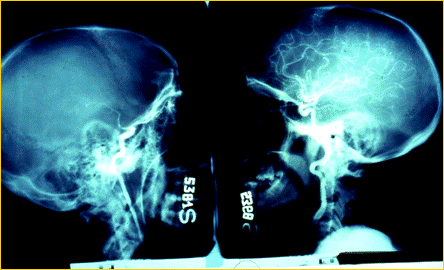

Le patologie che possono portare alla morte cerebrale sono l'emorragia cerebrale da rottura di un vaso intracranico, i traumi cranici ( incidenti stradali, ferite da proiettile ), le neoplasie cerebrali primitive.

EMATOMA SUBDURALE FERITA DA PROIETTILE

L'accertamento della morte cerebrale è competenza di un'equipè medica formata da un neurologo, un rianimatore ed un medico legale e dopo tale accertamento deve trascorrere un periodo di osservazione di sei ore prima che possa essere effettuato il prelievo degli organi.